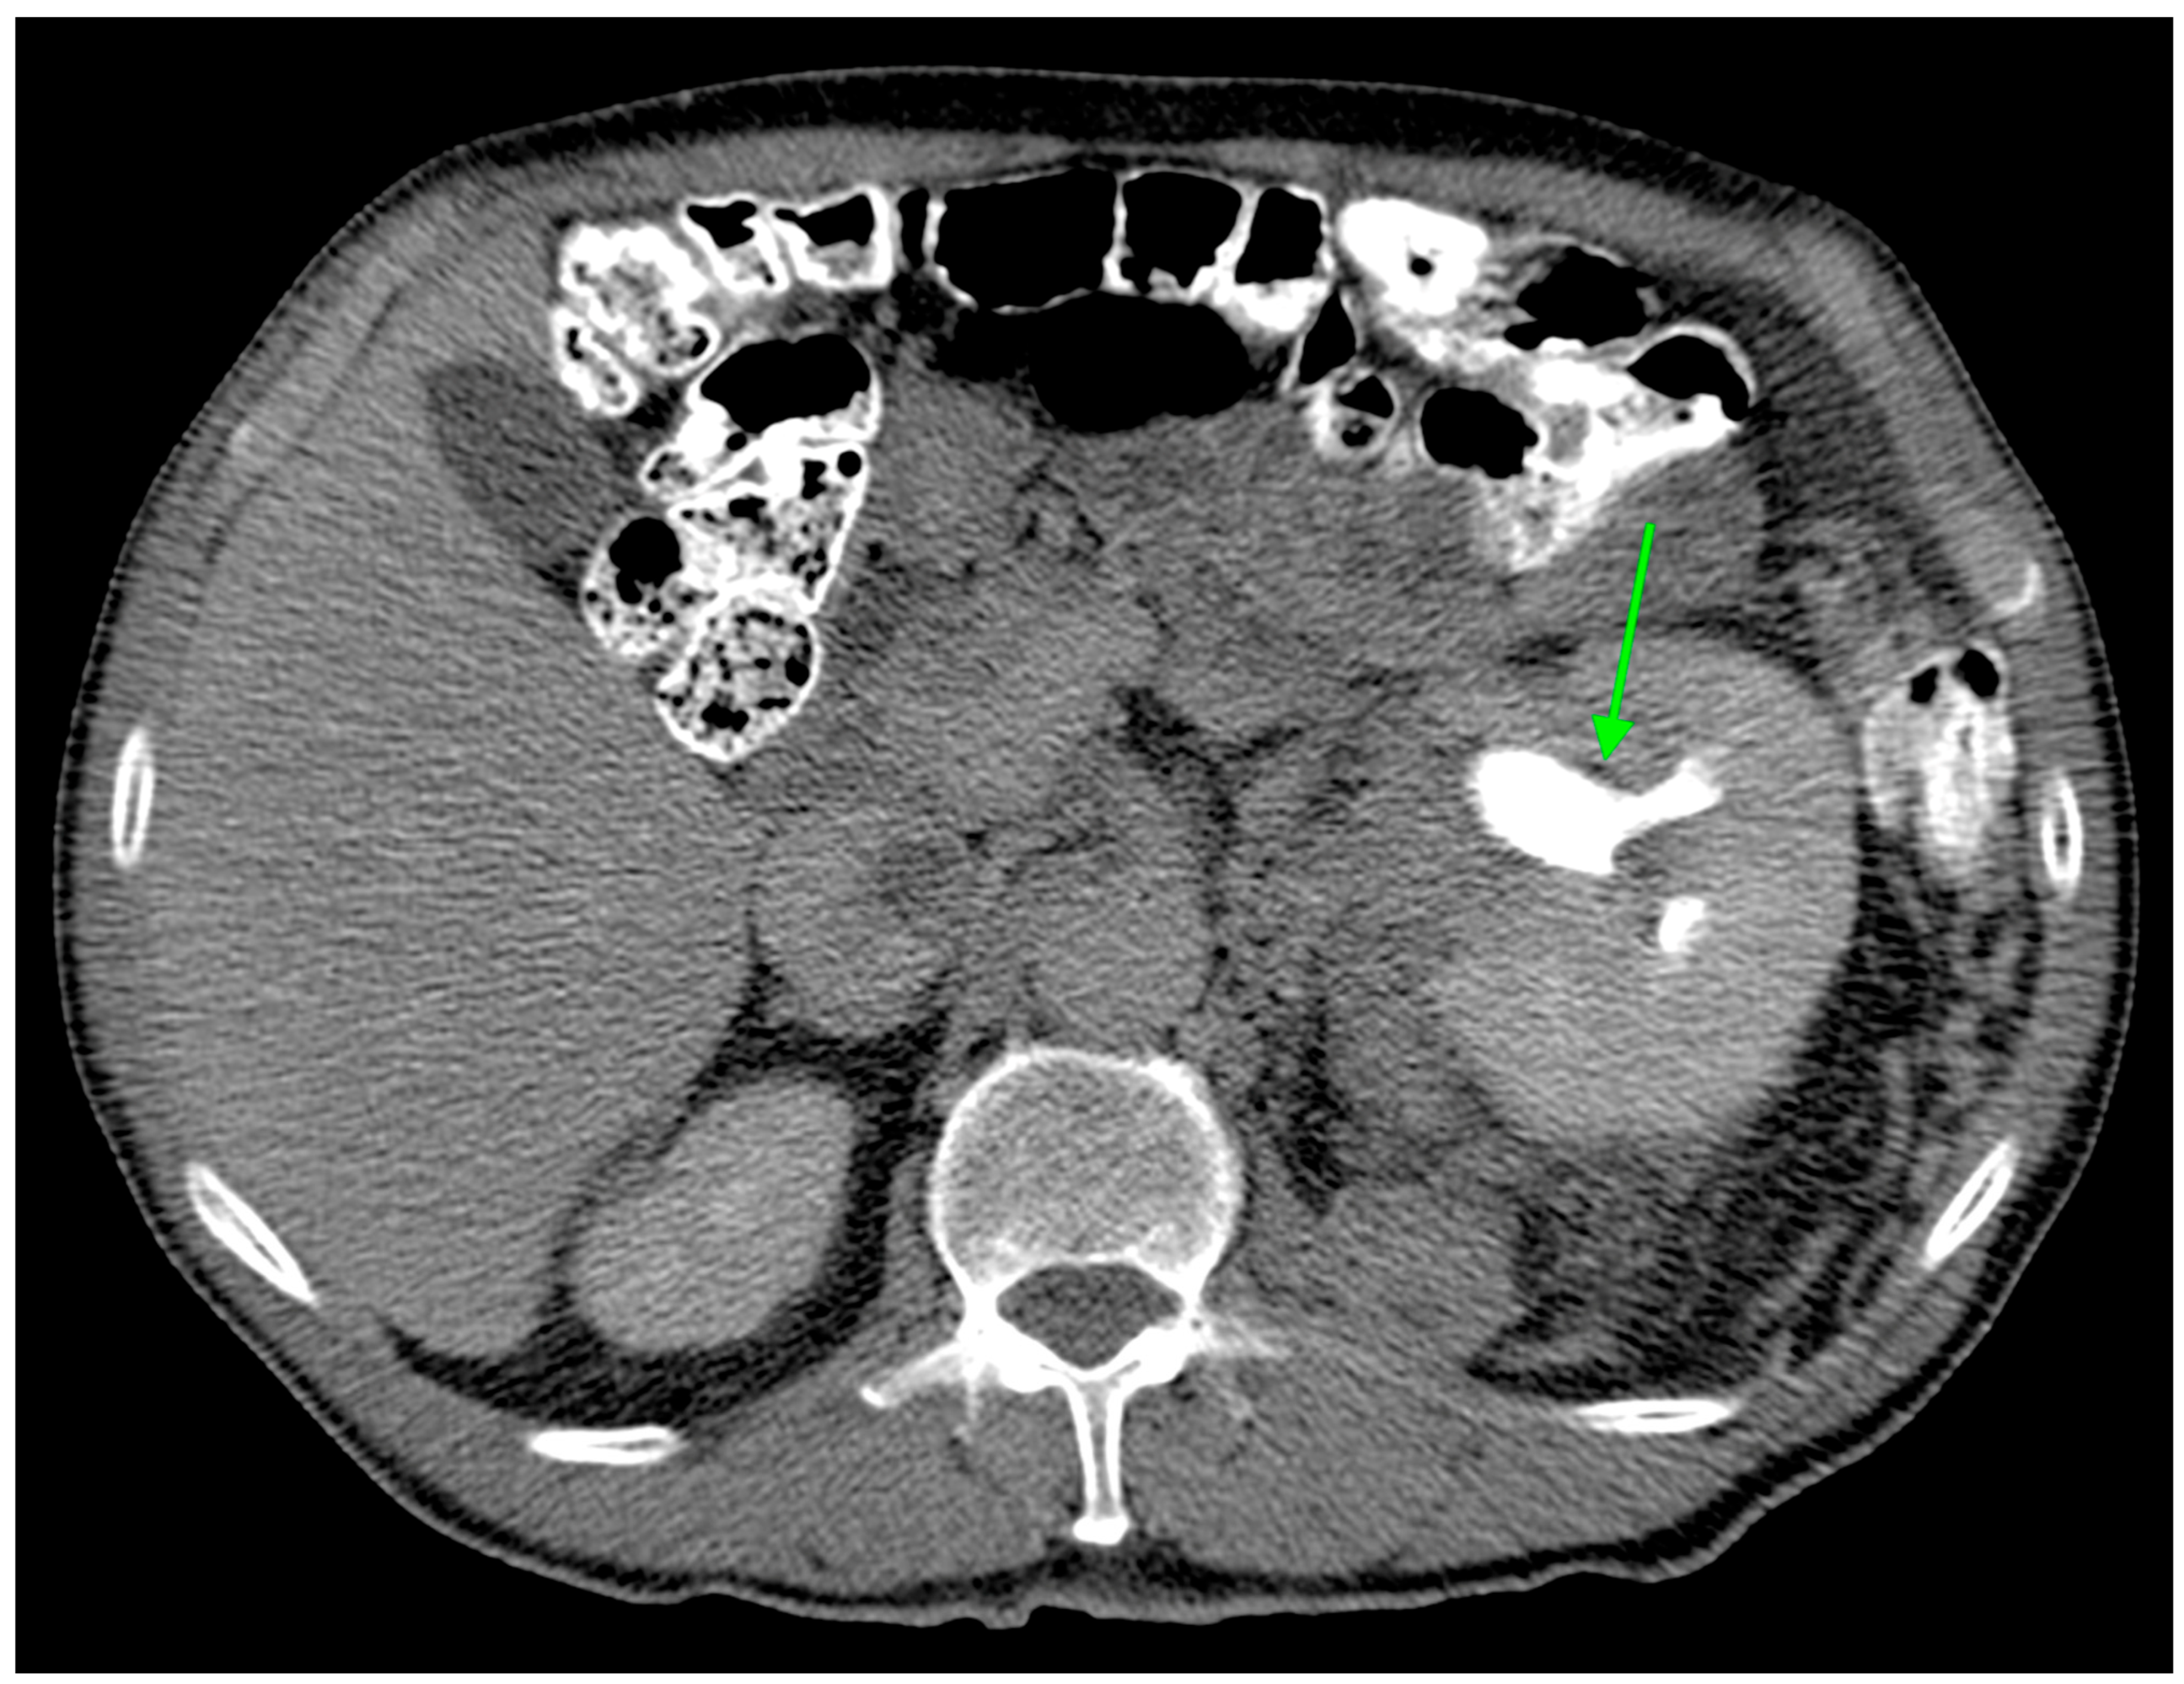

In this study, we evaluated the CT features of ADFP expression in ccRCC patients. A significant correlation was found with hydronephrosis (p = 0.025) (Figure 2). Furthermore, greater quantities of TAT, VAT, and SAT were found in low-Fuhrman-grade ccRCC patients with ADFP expression compared to high-Fuhrman-grade ccRCC patients with ADFP expression (p = 0.004, p = 0.003 and p = 0.045, respectively) (Figure 3). Significantly lower tumoral HU values were found in low-Fuhrman-grade ccRCC patients with ADFP expression compared to high-Fuhrman-grade ccRCC patients with ADFP expression (p = 0.002) (Figure 4), and significantly lower values of tumoral HU in low-Fuhrman-grade ccRCC patients without ADFP expression were found compared to high-Fuhrman-grade ccRCC patients without ADFP expression (p = 0.021).

Figure 2.

Axial CT image during excretory phase showing ccRCC with AFDP gene expression with hydronephrosis (green arrow).

Hydronephrosis was found to be a radiogenomic feature of ccRCC with ADFP expression (Figure 2). This link could be due to an indirect association. For instance, ADFP’s role in lipid metabolism might influence tumor characteristics such as size, invasiveness, or vascularity, which in turn could contribute to the development of hydronephrosis due to tumor obstruction, making hydronephrosis a typical feature of ccRCC with ADFP expression.